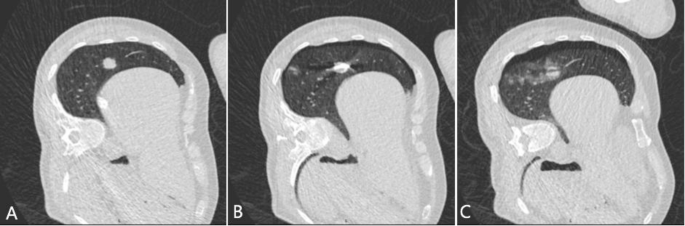

Spectral shaping technology (100Sn kV) CT-guided microwave ablation of lung tumor. A 54-year-old male patient, with a height of 1.70 m, weight of 63 kg, and a BMI of 21.80. He had a solid nodule in the lower lobe of the right lung, and the pathological result was lung metastasis of rectal cancer. He received spectral shaping protocol CT-guided lung tumor MWA. The local scan radiation dose was 0.056 mSv, and the overall radiation dose during ablation was 0.77 mSv for this patient. A Preoperative local lesion scan clearly shows the solid nodule. B During the puncture process, the ablation needle punctures to a satisfactory ablation site. C Immediate whole lung scan images after ablation show that the lesion was completely covered by a ground glass halo and that there was a small amount of bleeding at the puncture site.